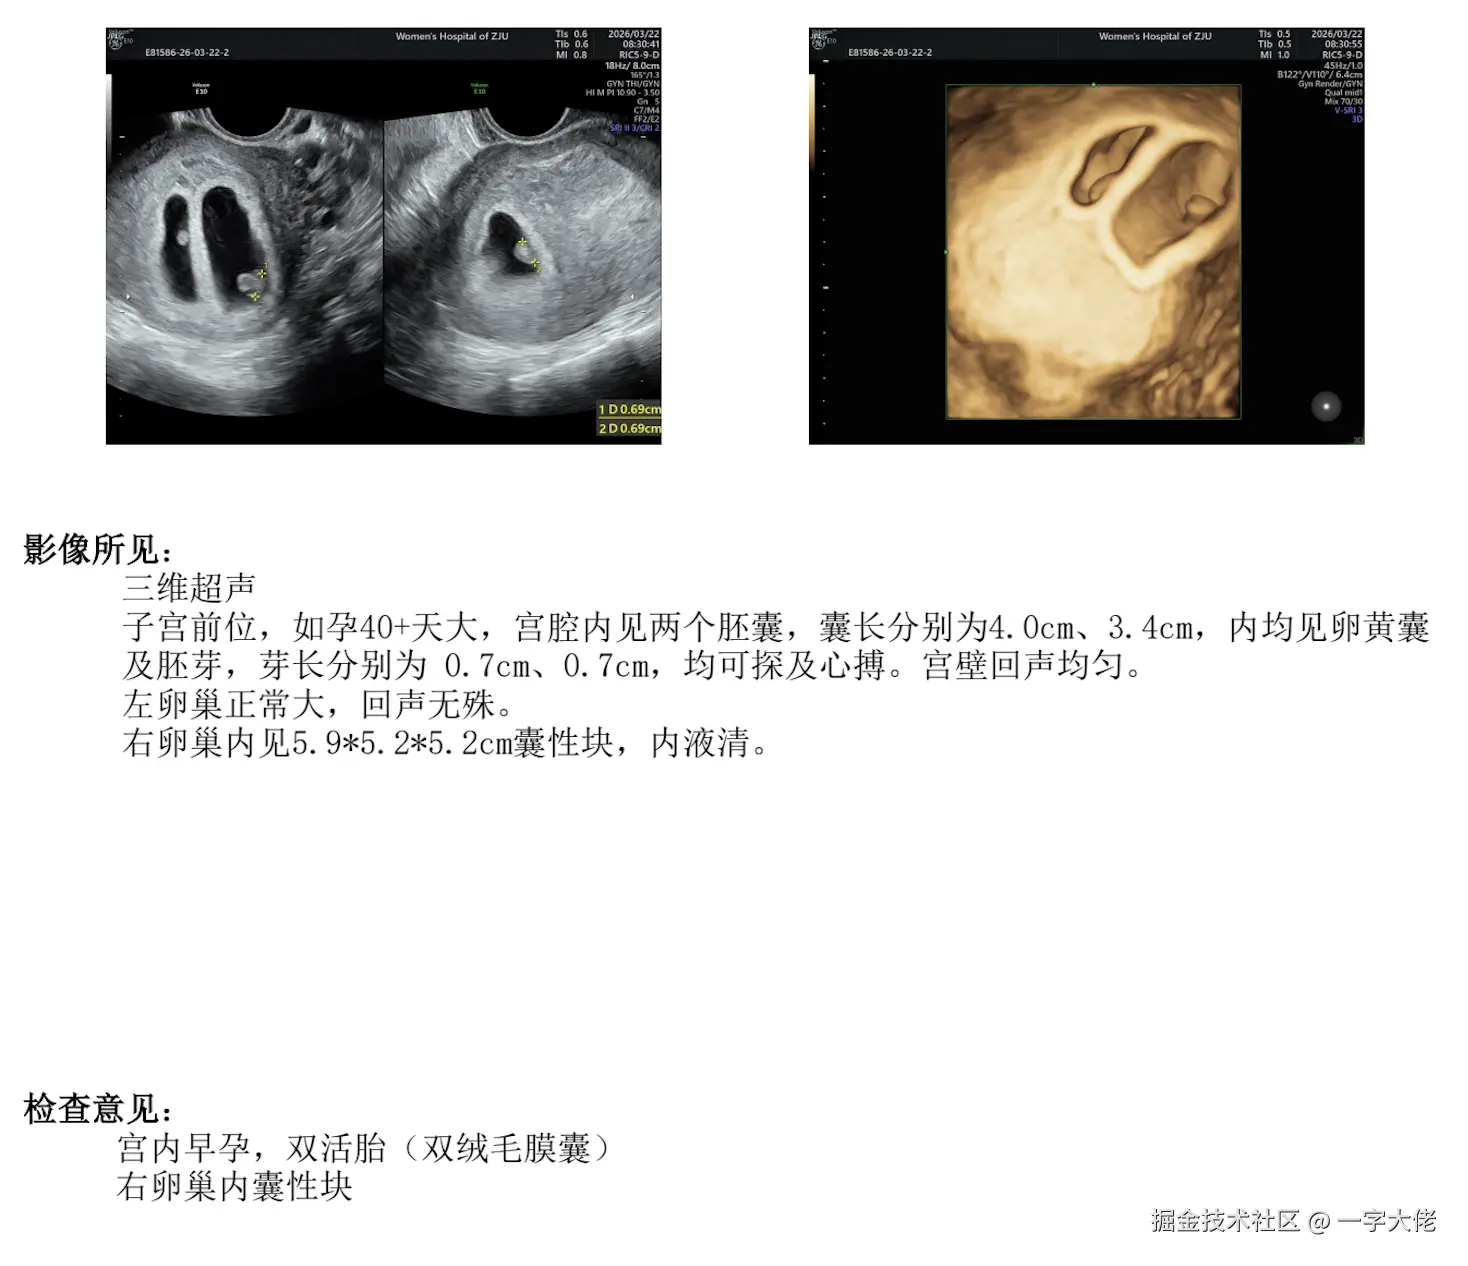

后面,她回来了,(两边家长都知道这事,说看我们自己决定)说还是不想这么早要孩子,我就陪着她去医院做检查,准备不要宝宝,但是后面检查说是有囊肿,现在不要孩子以后可能有影响,我们又犹豫了,最后还是决定生下宝宝。